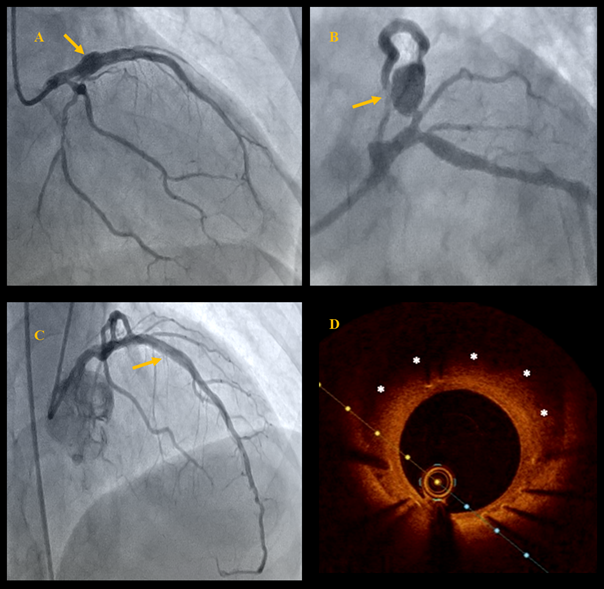

A 63-year-old man who was a smoker with no prior treatment for chronic diseases was admitted to the cardiology department with chest pain for the past 2 days due to non-ST-elevation acute myocardial infarction. Transthoracic echocardiography showed a left ventricular ejection fraction (LVEF) of 30% and akinesia of the inferior wall, interventricular septum, and apex. Coronary angiography revealed multivessel coronary artery disease without significant lesions in the right coronary artery (RCA) and with a prominent coronary artery aneurysm (CAA) in the proximal segment of the left anterior descending artery (LAD), as well as concomitant significant stenosis in LAD segments 6 and 7 and the marginal artery (Figure A and B, Video 1).

The heart team decided to perform percutaneous coronary intervention (PCI). The first stage involved PCI of the left main artery (LM) and LAD via the right radial approach with implantation of 2 zotarolimus-eluting stents (3.5 x 30 mm and 3.5 x 34 mm), and PCI of the circumflex artery (Cx) with a drug-coated balloon. The procedure led to improvement of flow through the LAD and residual filling of the aneurysmatic sac (Video 2). Further in-hospital stay was uneventful. The patient received dual antiplatelet therapy and statins and was scheduled for cardiac rehabilitation and follow-up angiography in 3 months. At the 3-month follow-up, echocardiography showed LVEF improvement to 45%. Follow-up coronary angiography confirmed a good PCI result (Figure C, Videos 3 and 4), and optical coherence tomography revealed full stent strut coverage, moderate neointimal hyperplasia, and complete sealing of the aneurysm cavity with endothelialized stent struts (Figure D).